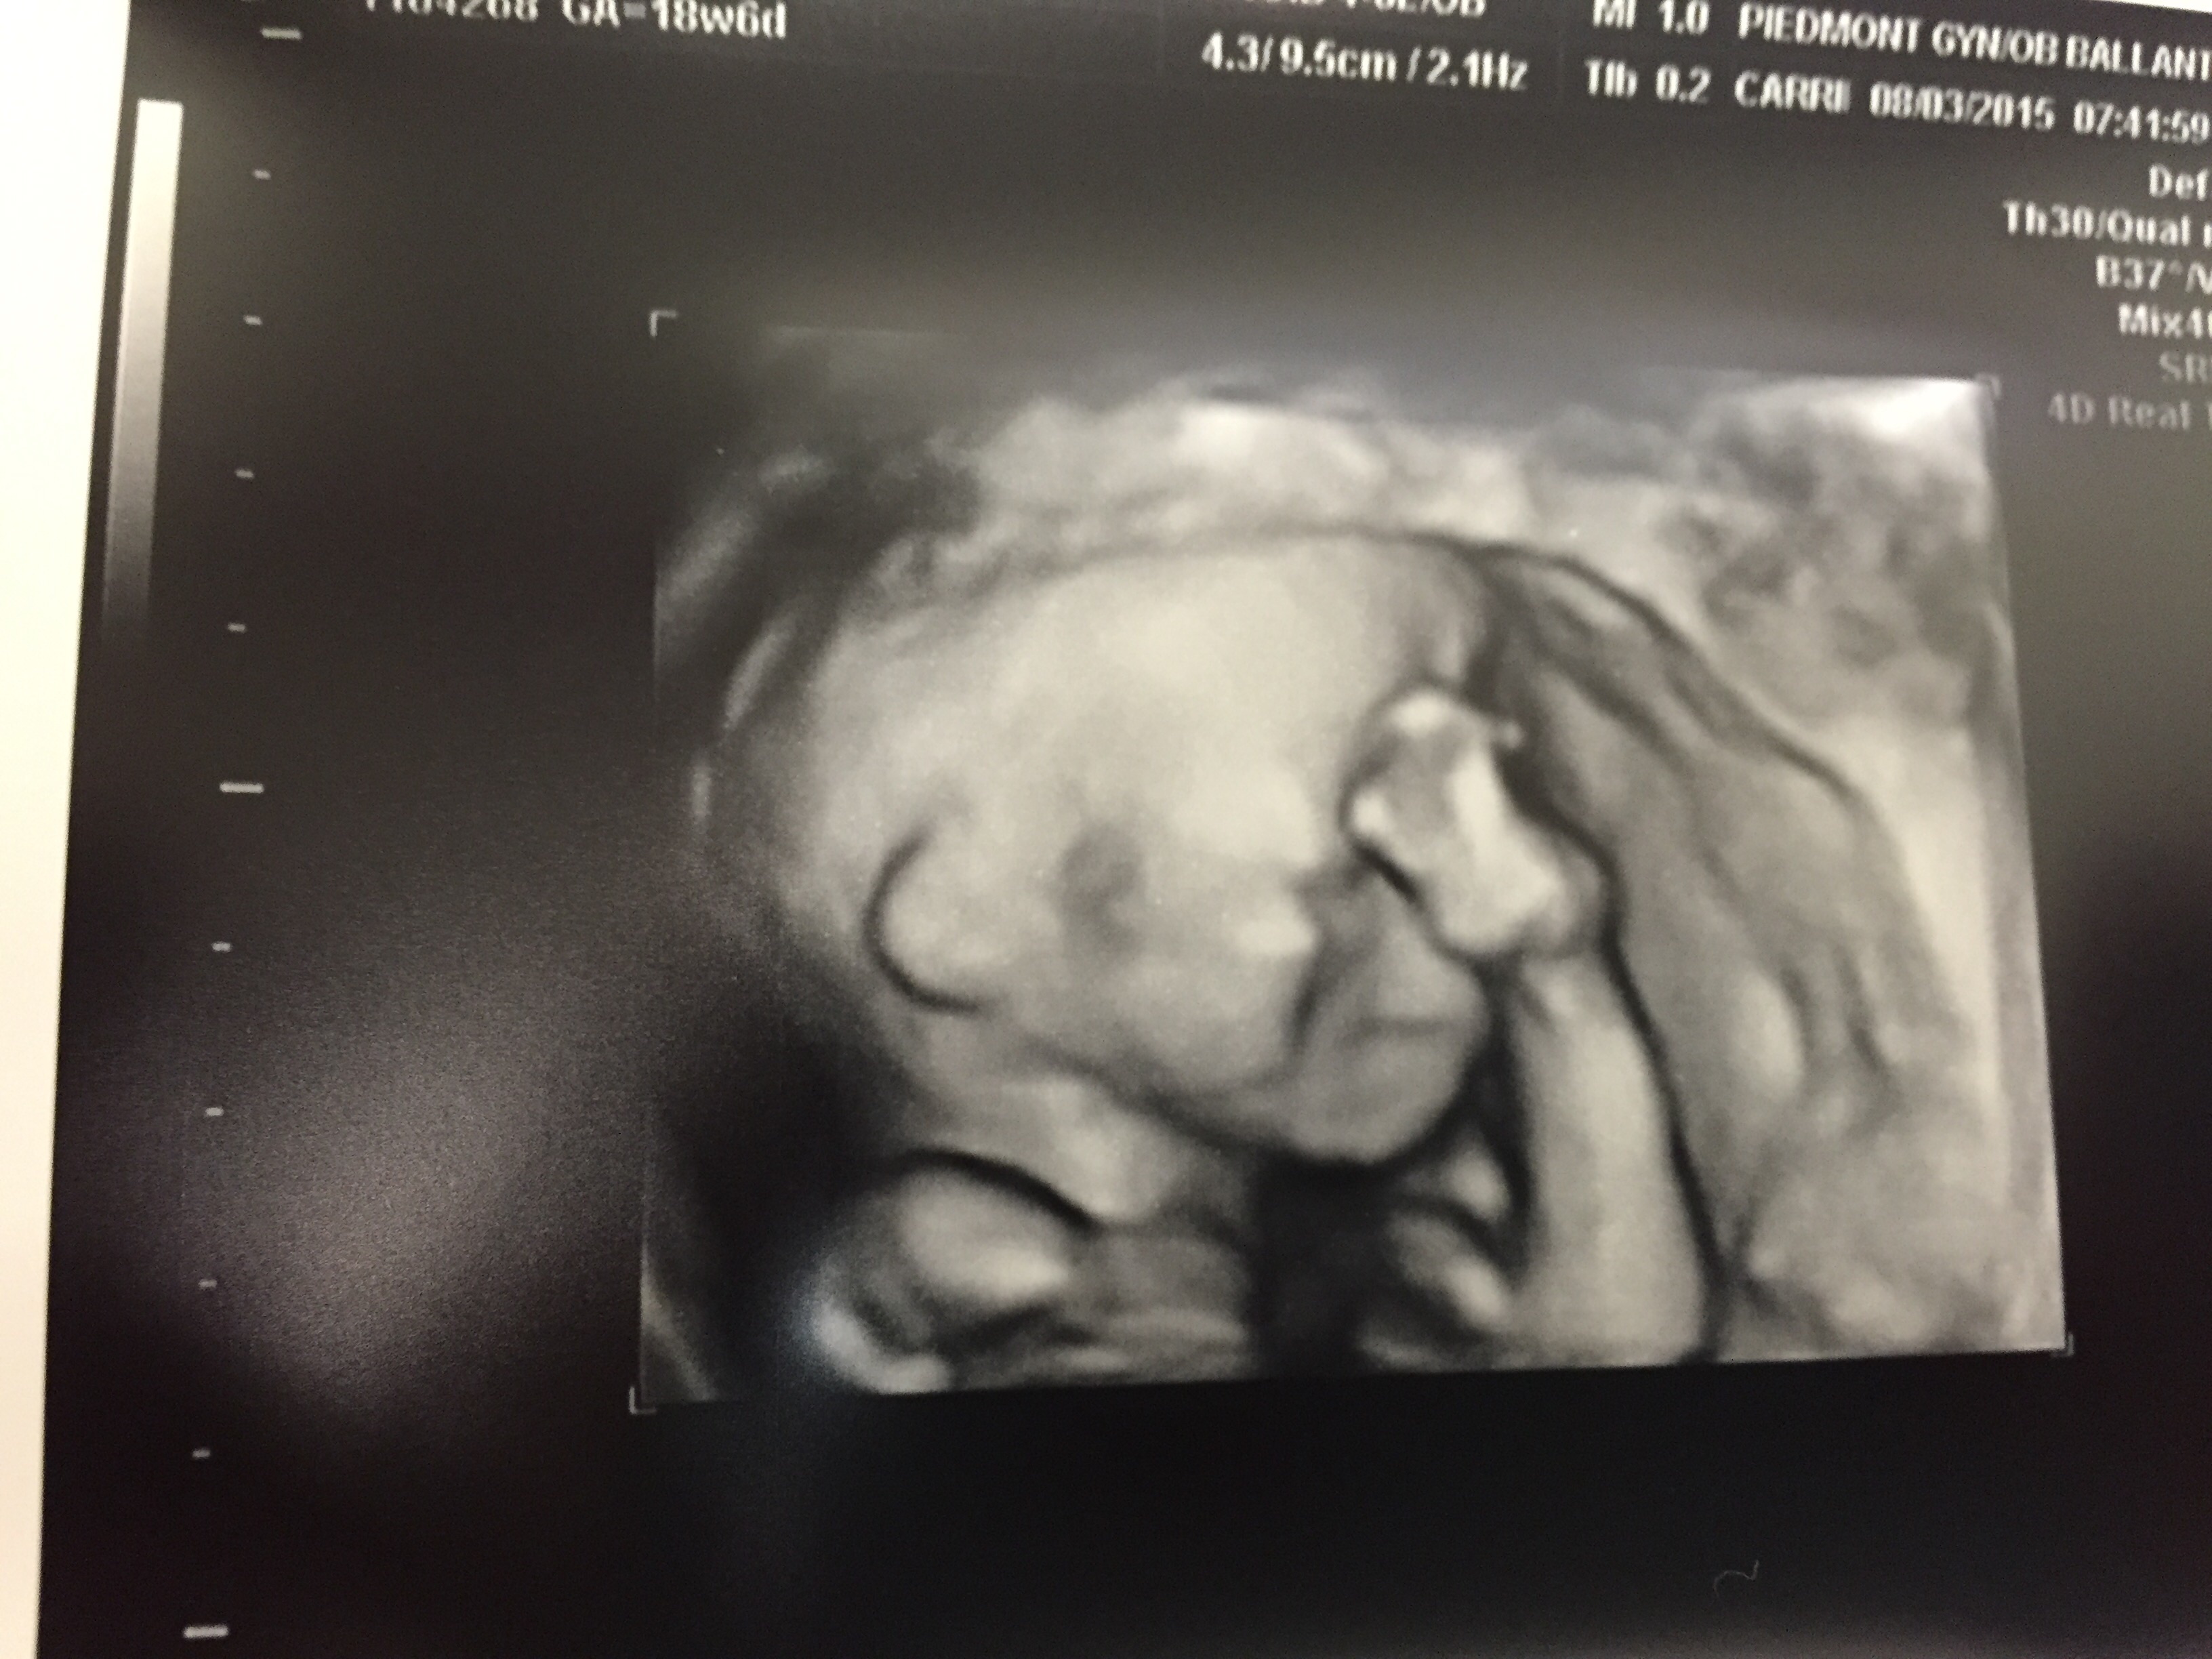

• Here's our little guy

Hello ladies, I'm a ftm and had Anatomy scan today. We found out we are having a wonderful little boy!!! Although I'm overjoyed with excitement, the scan revealed that our little angel has club feet. We are devastated as first time parents. We have a follow up apt tomorrow to get a better look at the women's institute. Anyone have experience with this? What to expect? The doctor also told us that club feet have a very small link to Down's syndrome, so we had to get the Harmony blood test as well. We have no family history of anything significant and were definitely not expecting this!! We now have a entire week of agonizing worrying until the test come back.